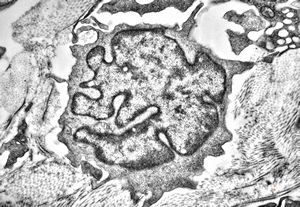

M, 48y. | multiplication of dermal perivascular basement membranes (unclassified myopathy)